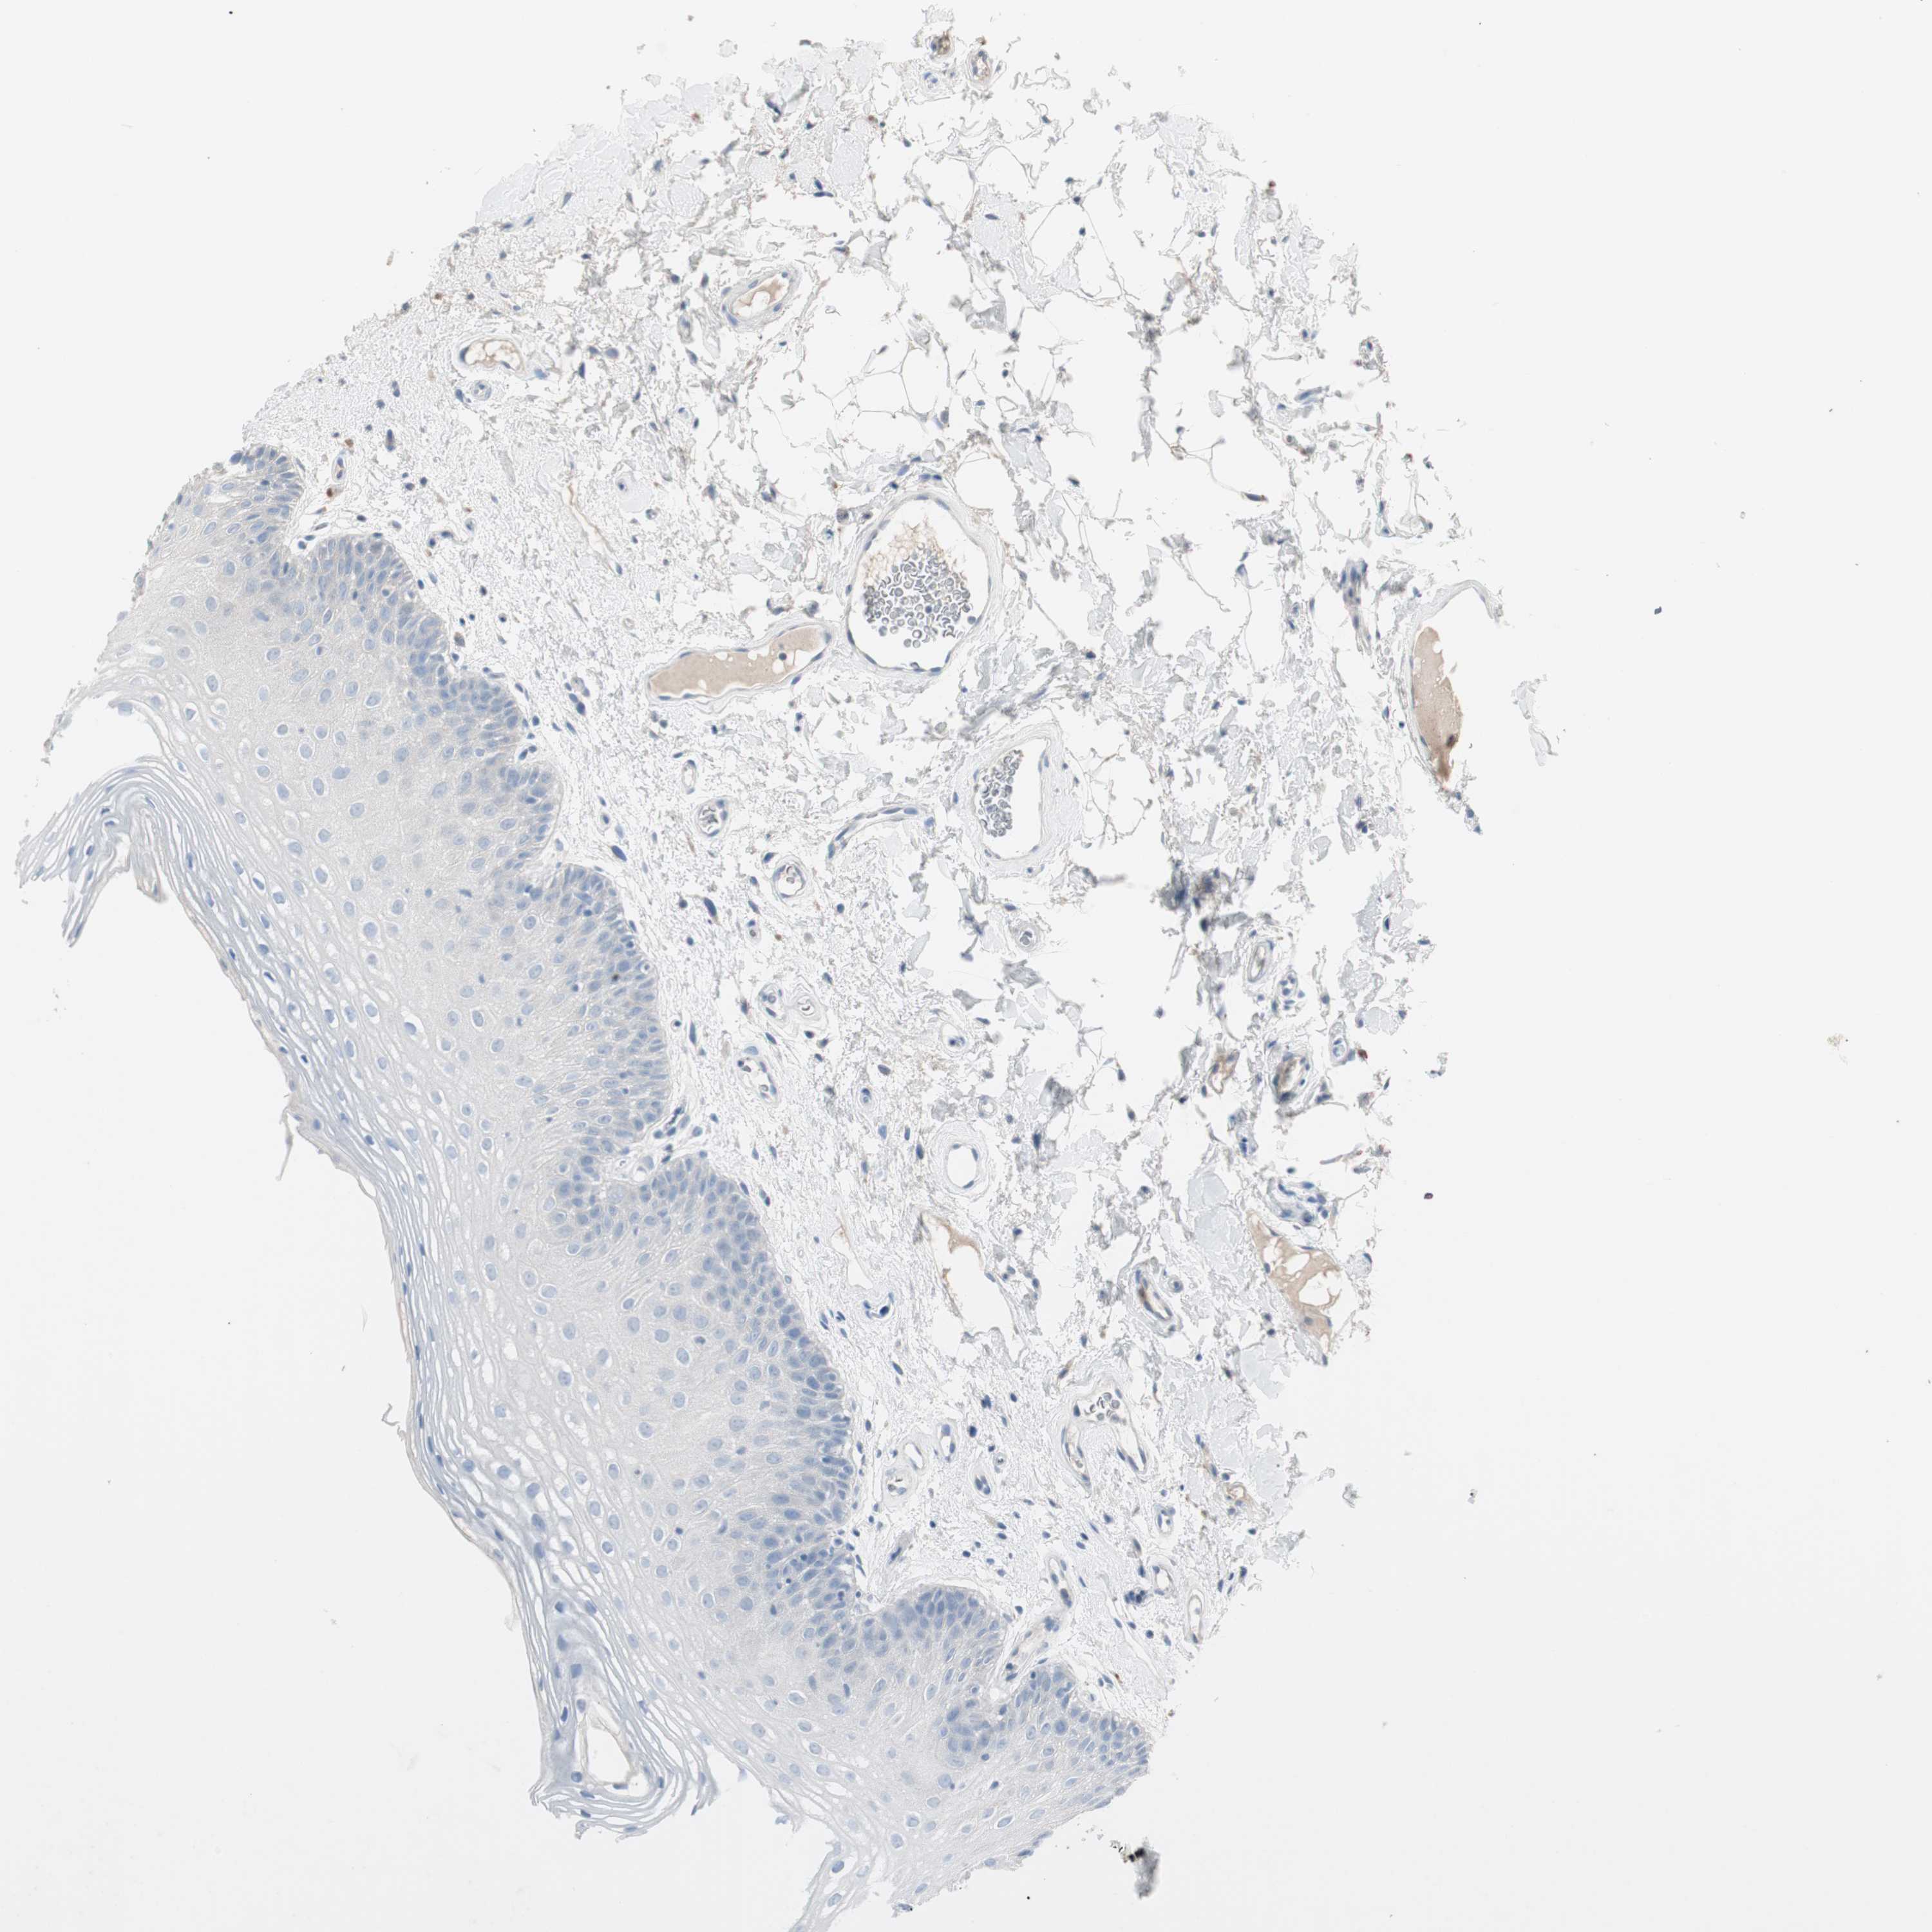

TISSUE PRIMARY DATA ORAL MUCOSA Show tissue menu

ORAL MUCOSA - Antibody stainingi

Antibody staining in the annotated cell types in the current human tissue is reported as not detected, low, medium, or high, based on conventional immunohistochemistry profiling in selected tissues. This score is based on the combination of the staining intensity and fraction of stained cells.

Each image is clickable and will lead to virtual microscopy that enables deeper exploration of all samples and also displays staining intensity scores, fraction scores and subcellular localization as well as patient and tissue information for each sample.

Antibody HPA007040

Squamous epithelial cells Not detected